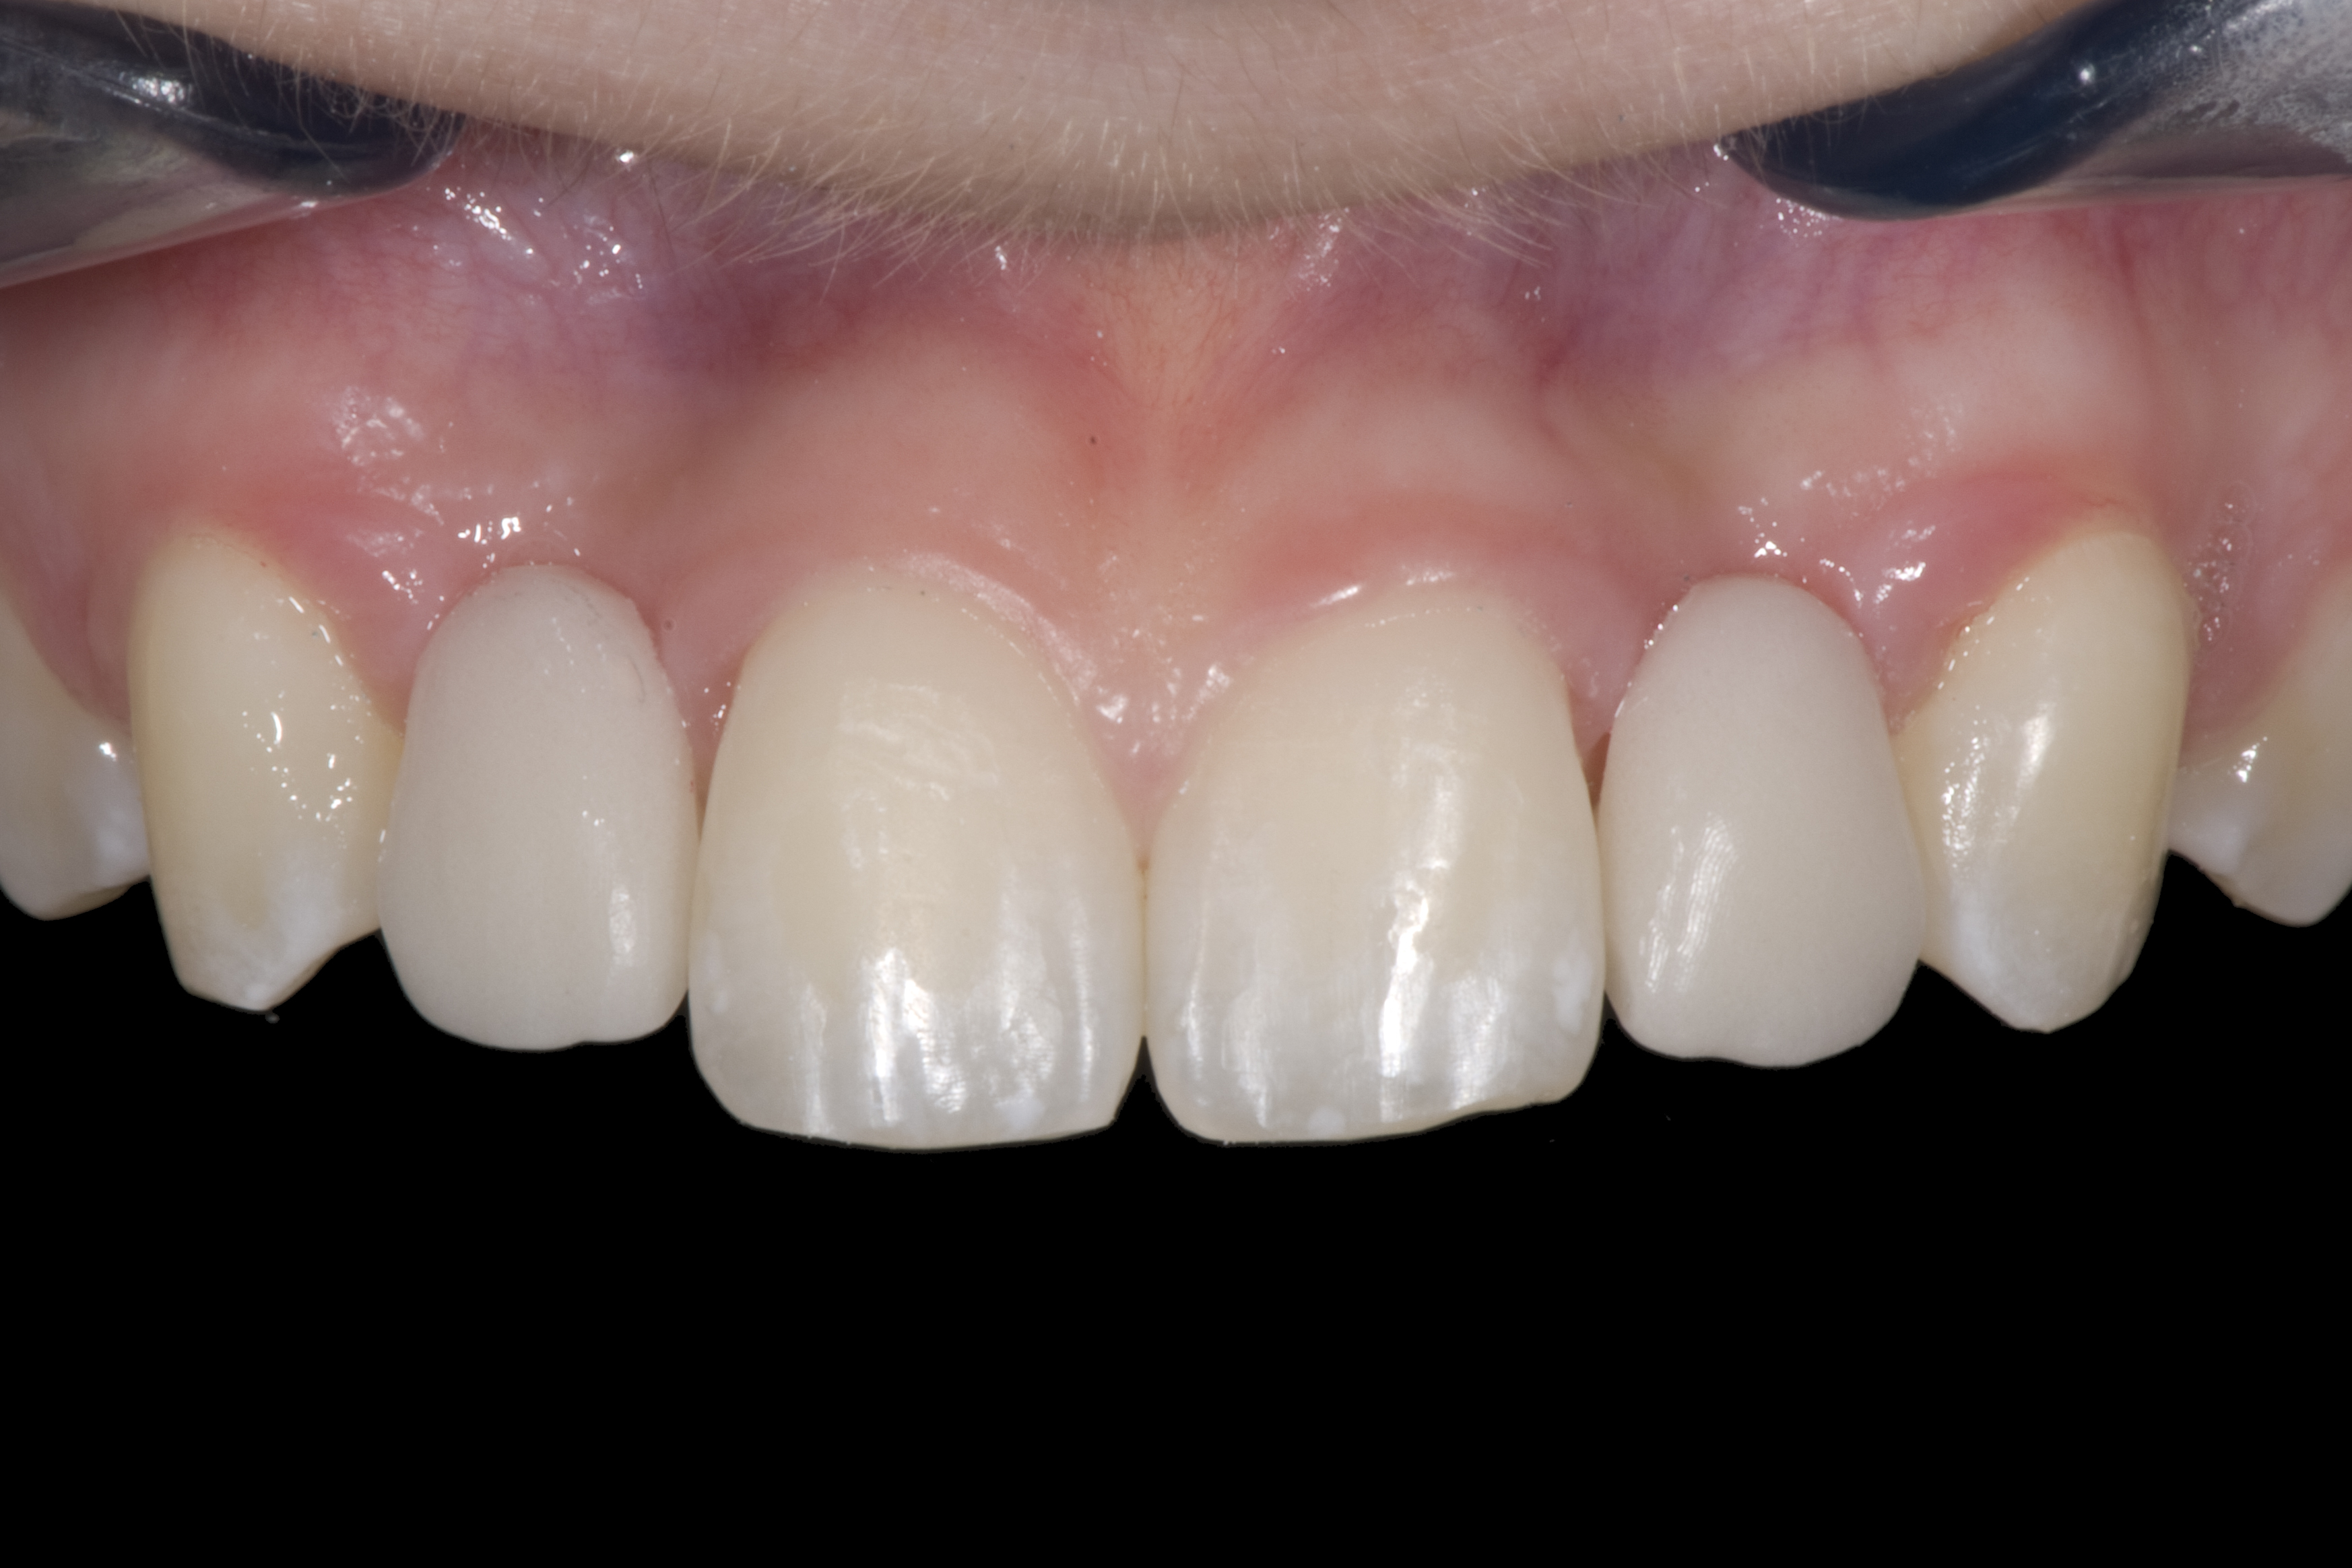

(20.) Facial view of final single-wing, modified zirconia resin-bonded bridges.

Figure 20

(21.) Smile view.

Figure 21

When the patient returned, the fit was evaluated in the mouth. Once verified, the internal surface of the framework was etched with a 9.5% hydrofluoric acid for 90 seconds and then salinized. After etching the enamel surface with phosphoric acid for 30 seconds and applying the primer (Single Bond Plus, 3M ESPE) to both the internal surface of the framework and the enamel, the zirconia bridge was bonded with a dual-cure resin cement (RelyX™ ARC, 3M ESPE). After the procedure, the patient ended up with a long-term, high-strength esthetic restoration advantaged by the bonding potential of fledspathic ceramic (Figure 20 through Figure 24). Six years after placement, the prosthesis had remained in place with no complications.